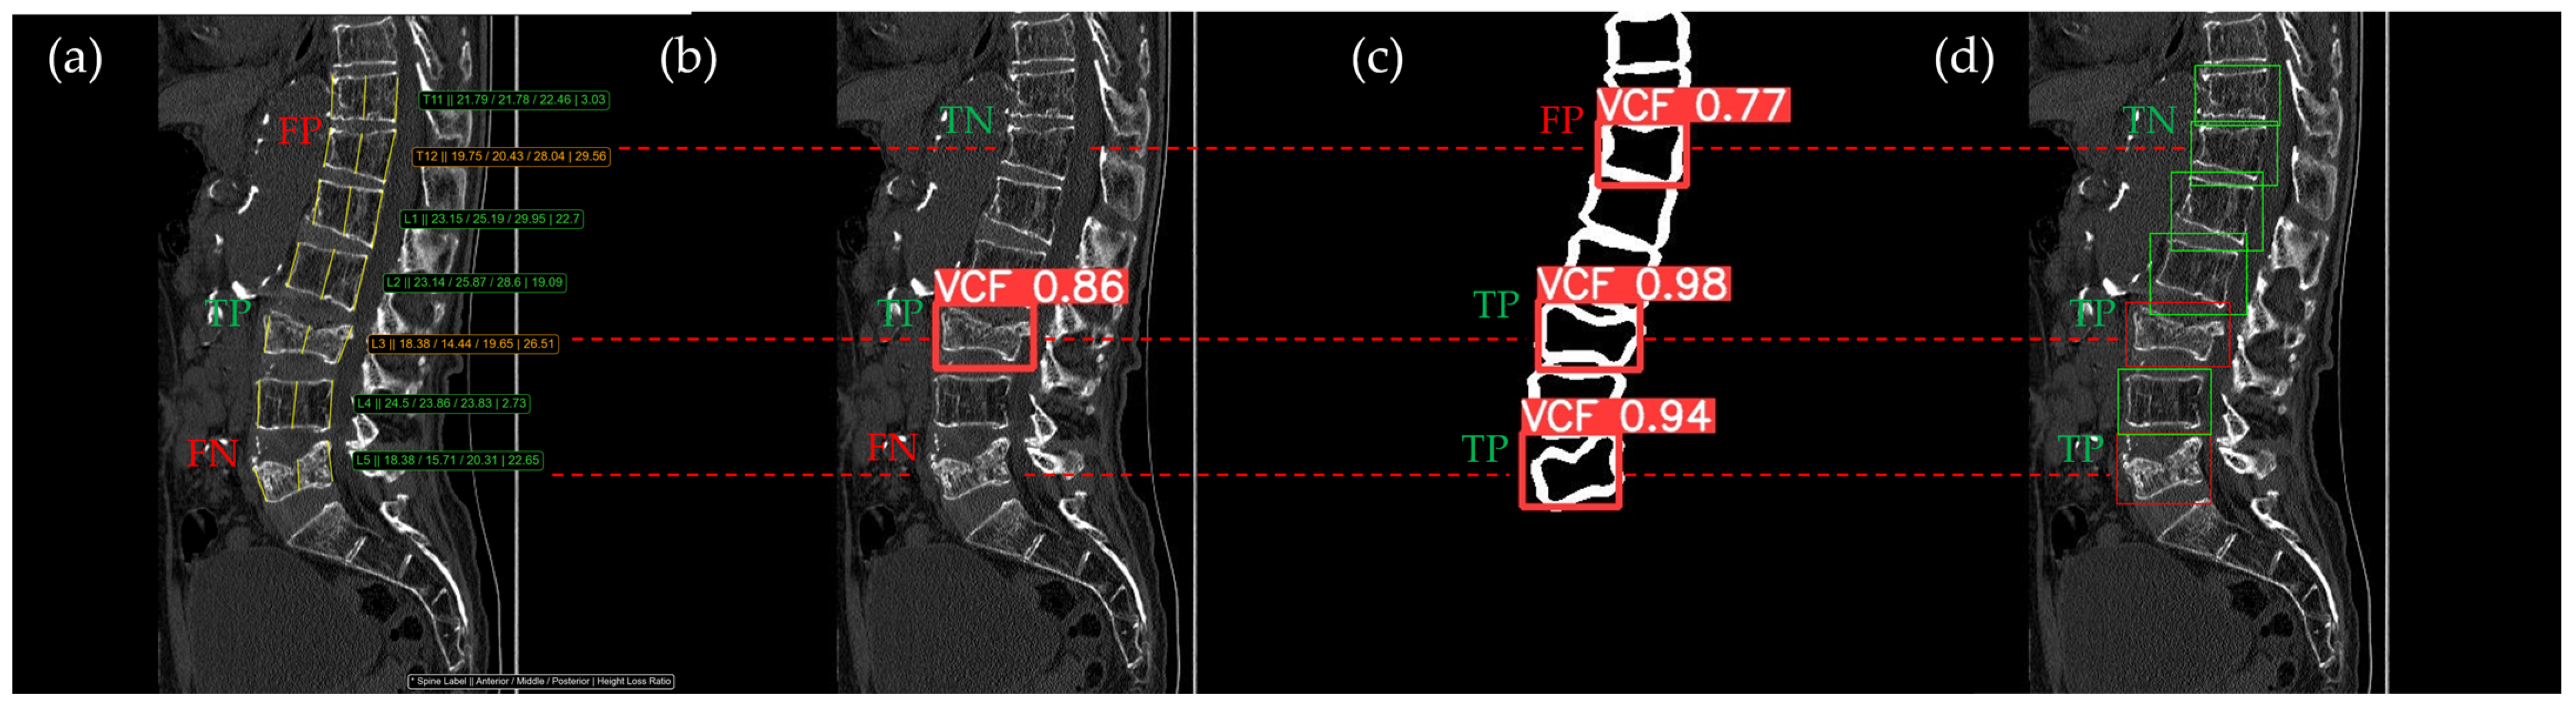

Figure 10, Figure 11, Figure 12, Figure 13 and Figure 14 illustrate typical examples of results for HLR, EEVD, TSVD_SD, and TSVD_DC in patients with acute VCFs. The results of applying different methodologies to the same patient image and identical slice locations were as follows. In the HLR results, each vertebra was marked with yellow solid lines indicating the height measurement lines for the anterior, middle, and posterior regions. The measured height values and HLR percentages were displayed on the right side of the image. If the HLR percentage ranged between 25% and 40%, it was highlighted in orange, while values of 40% or higher were highlighted in red. In the EEVD results, the VCF detection outputs were displayed along with their respective confidence scores based on the input patient images. For the TSVD_SD results, after performing spine segmentation, the model extracted only the spine contour, and the VCF detection results with their corresponding confidence scores were presented. In the TSVD_DC results, bounding boxes were generated for each vertebral body, with normal vertebrae represented in green and vertebrae identified as VCFs displayed in red.

The VCF detection results from four different methods. (a) HLR, (b) EEVD, (c) TSVD_SD, and (d) TSVD_DC. The acute VCF, as confirmed by the radiologist, was located at the L1 level. TP, TN, FP, and FN were marked at the same level with a red dotted line.

Figure 13.